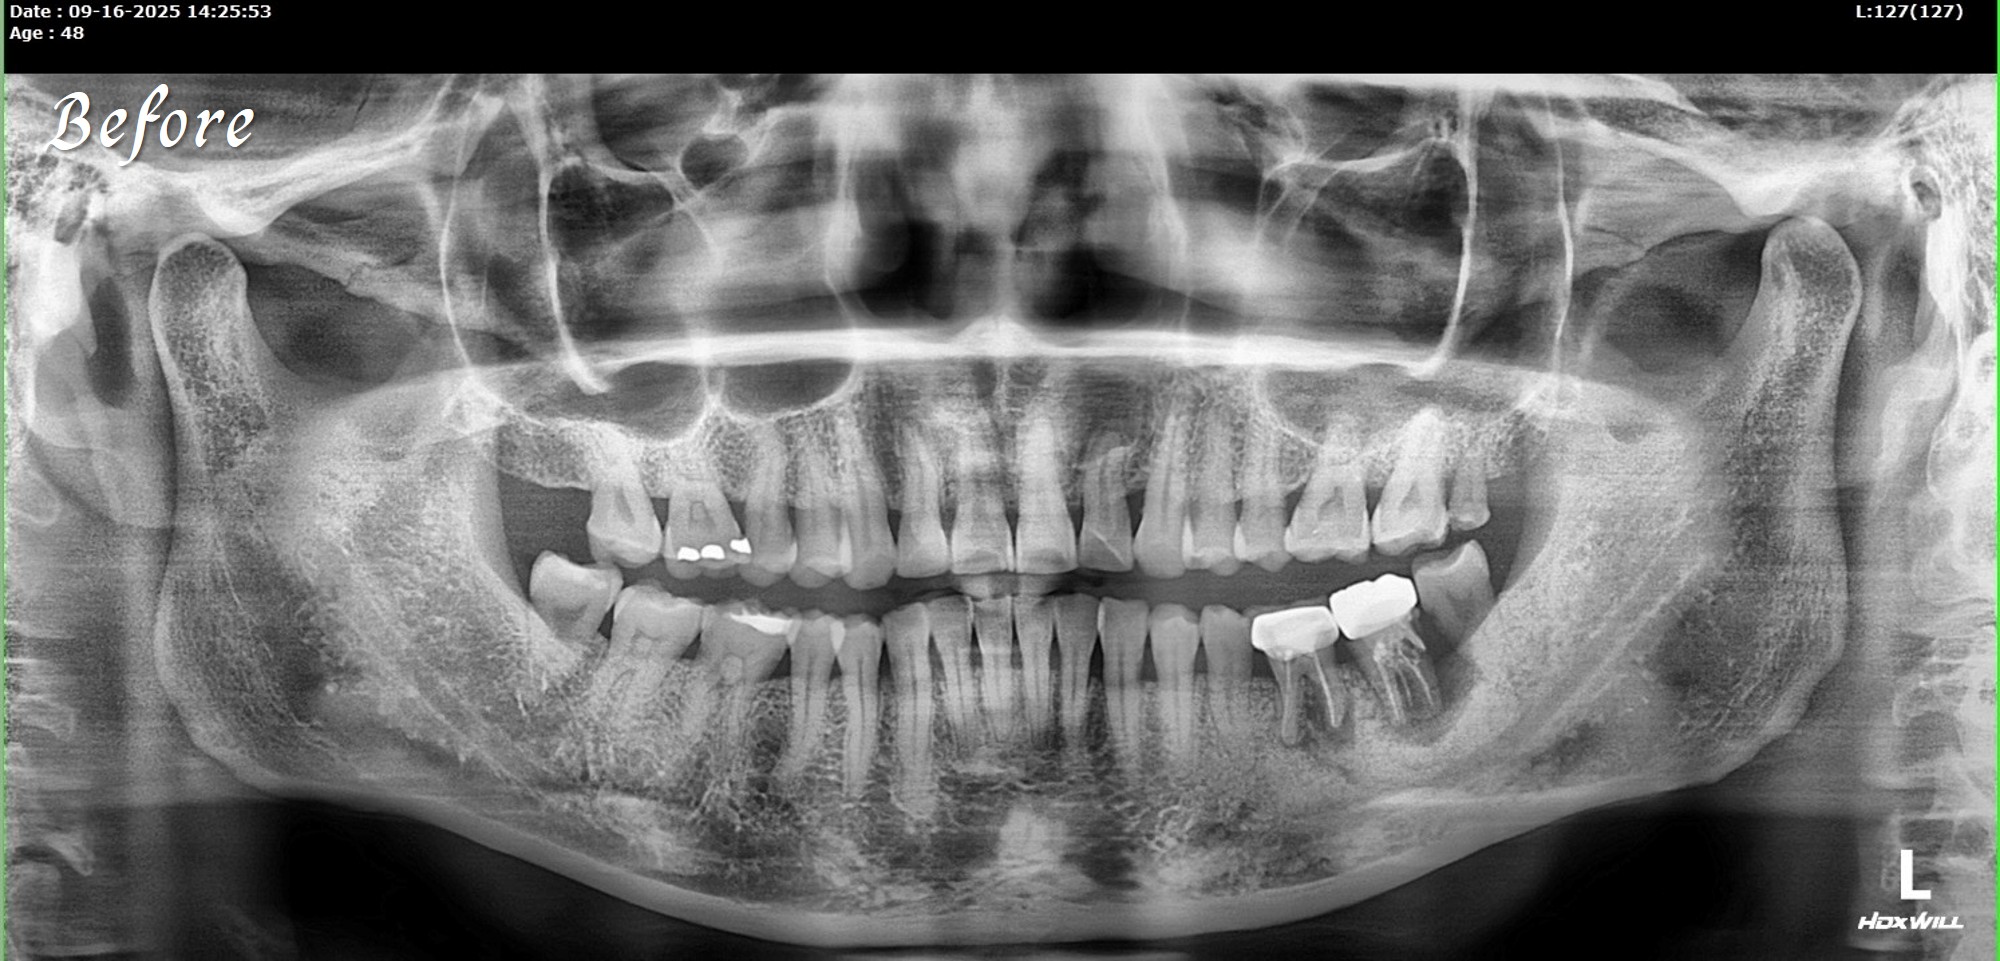

一位初診新患者,陳博士評估後進行治療。

若以一般傳統流程,往往需要先拔牙後等待數月,

再補骨、放人工膜,等待約10 個月左右,

之後還得再取出人工材料才能進行植牙,

整個療程動輒一年以上,空窗期長,變數也多。